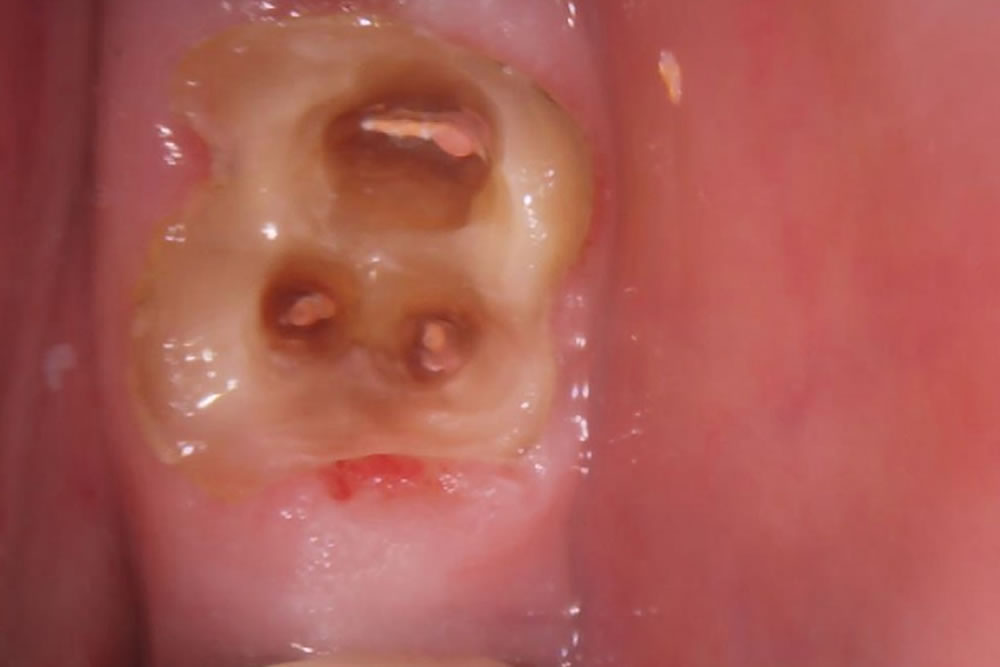

根管治療を行うためには被せ物と土台を外す必要があります。奥歯の被せ物は連結していたため切断し、被せ物と金属の土台も外していきました。

被せ物と土台を外したため、過去に根管治療を行った際のゴム状の材料が見えている状態です。